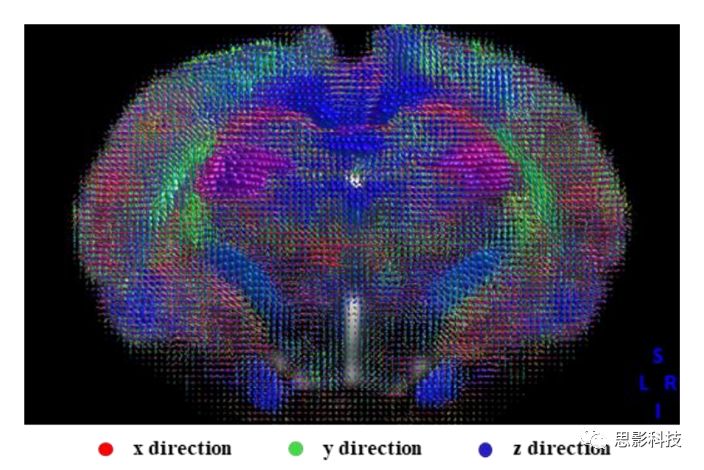

3、纖維追蹤

思影可根據(jù)不同的數(shù)據(jù)類型以及客戶的不同需求,可采取多種彌散模型(如彌散張量模型DTI、約束球形反卷積CSD、彌散譜成像DSI等等)

基于不同模型的確定性纖維追蹤

基于不同模型的概率性纖維追蹤